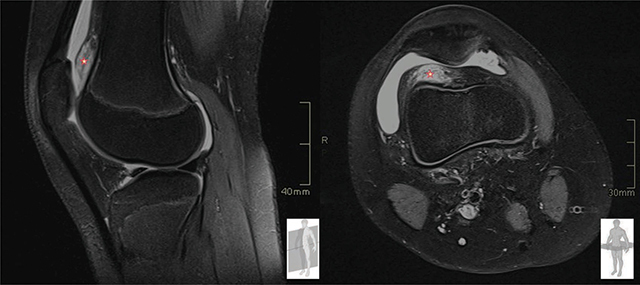

教学要点:股骨前脂肪垫撞击综合征是膝关节脂肪垫撞击的一种,可通过超声波检查进行评估。

Teaching point: Prefemoral fat pad impingement syndrome is one of the fat pad impingements of the knee and can be assessed with ultrasonography.